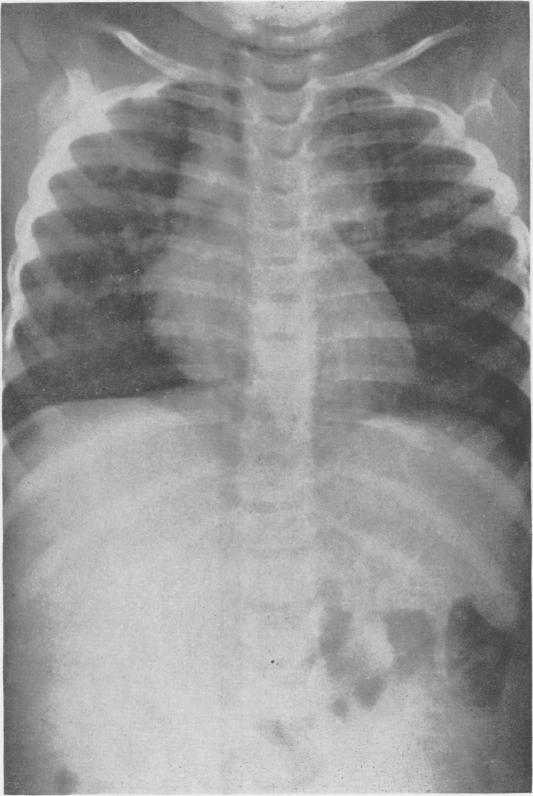

Bronchiogenic Cysts of the Mediastinum.